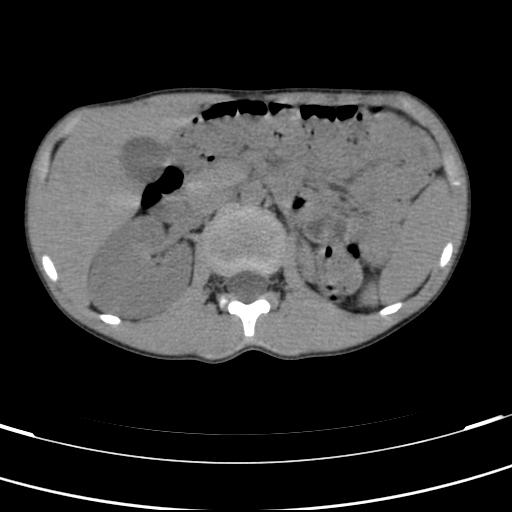

标题: PED3157:左肾缺如,请教脾脏的改变?、、

男孩,9岁。胃部不适。

脾脏位于左侧,但数个脾脏呈分离状态,左肾缺如,右肾代偿肥大。考虑多脾综合征。